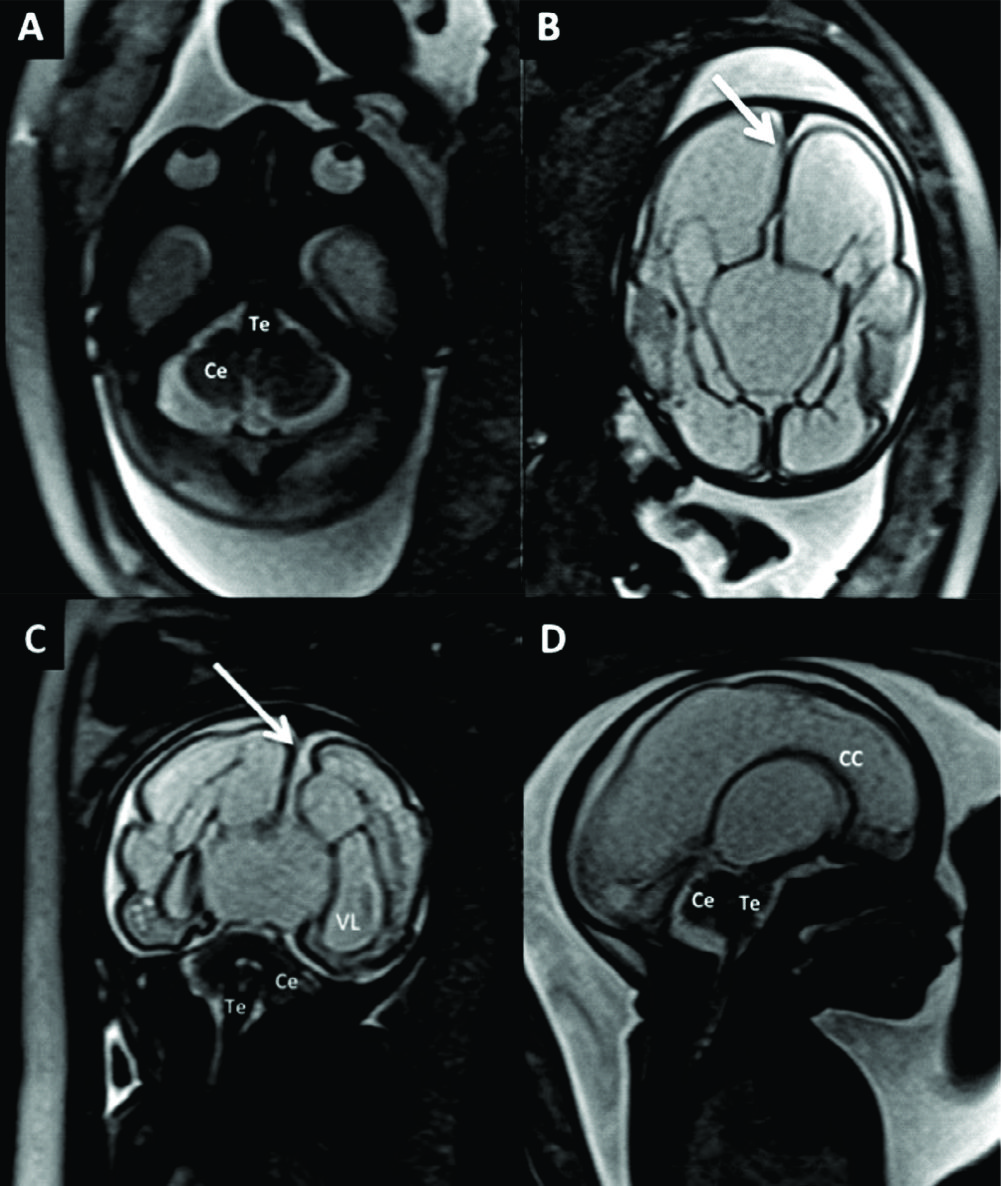

Figura 10

RM Fetal en Malformación de Chiari.

Estudio realizado a las 29 semanas con diagnóstico ecográfico de mielomeningocele. En imagen coronal (A) se observa la severa dilatación del sistema ventricular supra-tentorial lo que se corrobora en la imagen axial (B) con una disposición colpocefálica de los ventrículos laterales (VL). En la imagen fetal sagital (C) se reconocen el cerebelo (Ce) y tronco encefálico (Te) sin identificarse claramente el IV ventrículo lo que indica una disminución de las dimensiones de la fosa posterior. En el mismo plano se observa el defecto de cierre posterior del tubo neural (è) con un saco de meningocele. La imagen axial a nivel de ese saco (D) muestra claramente el defecto espinal posterior (è) aunque sin observarse claramente el contenido neural del mismo.